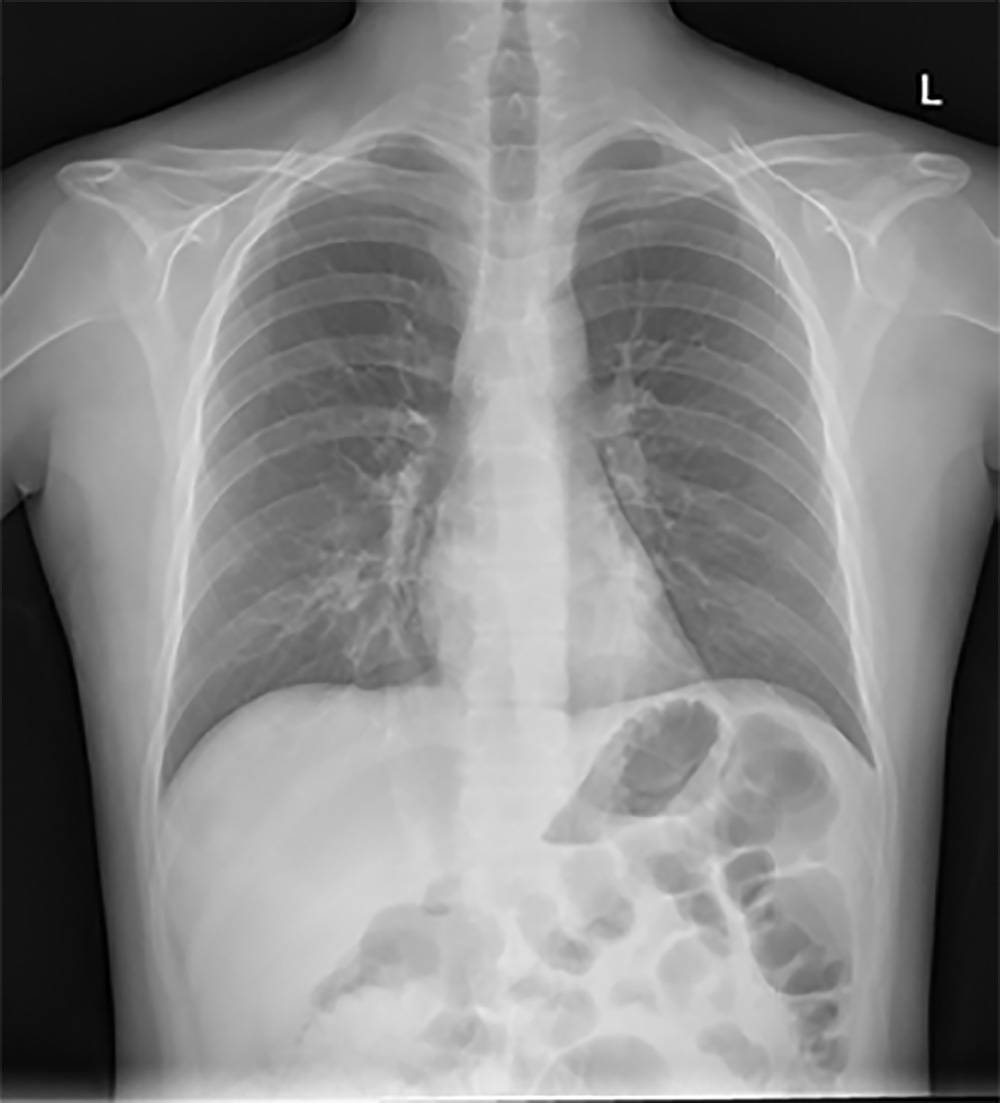

Após este período removeu-se o mesmo e efetuou-se uma radiografia de controlo. A radiografia evidenciou uma resolução completa do pneumotórax (Fig. 3), sendo programada a alta para o próprio dia.